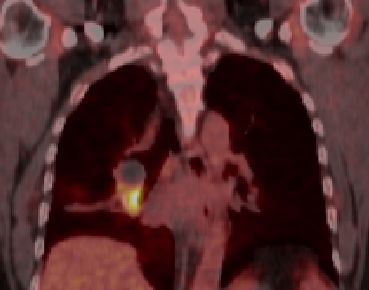

blauer Punkt 72-jähriger Mann, bei dem vor 2 Jahren ein Plattenepithelkarzinom des rechten Mittellappens operiert wurde. Bei asymptomatischem Verlauf im PET-CT ein Rezidiv im oberen rechten Hilus. Bronchusabsetzungsstelle frei!